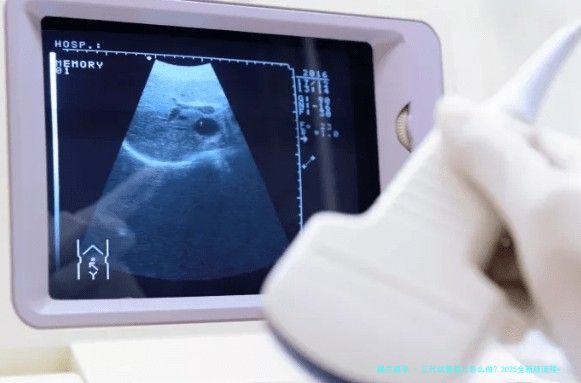

2.2 卵泡监测

在促排期间,须要定期进行阴道B超监测卵泡的成长情形,并通过抽血液检查测激素水平,比如E2和LH,来判断卵泡成熟度以及蕞佳采卵时间。